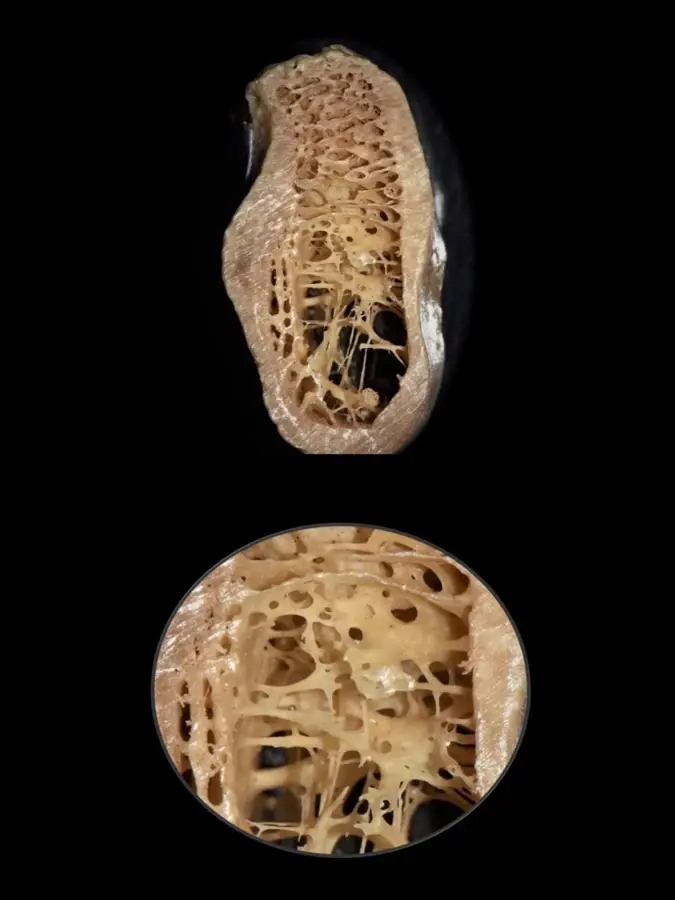

Cortes de la zona maxilar en los que se aprecia diferentes formación óseas como hueso cortical grueso y hueso esponjoso con espacios medulares amplios, cada una de las cuales requiere una indicación clínica específica.

Durante años, se establecieron las propiedades biomecánicas del hueso basándose únicamente en medidas a gran escala, pudiendo diferenciarse entre el hueso trabecular y el hueso cortical. Sin embargo, actualmente es posible un mayor análisis a nivel micrométrico que permite explorar entre los componentes orgánicos, tisulares, celular y moleculares. Es así que gracias a aproximaciones nanoestructurales se muestran asociaciones entre las propiedades biomecánicas y las calidades óseas, las que se pueden presentar tanto en el hueso cortical como en el trabecular de manera indistinta. En el cortical, el espacio poroso ocupa el 5-10%, mientras que en el trabecular se encuentra en el 30-90% del total de la estructura9 (Figura 1).

Figura 1. Sector postero-inferior de la mandíbula donde se aprecia una cortical gruesa y hueso esponjoso con espacios medulares amplios (arriba) y trabéculas bastante finas (debajo), muchas veces del espesor de un cabello (0,025 mm).